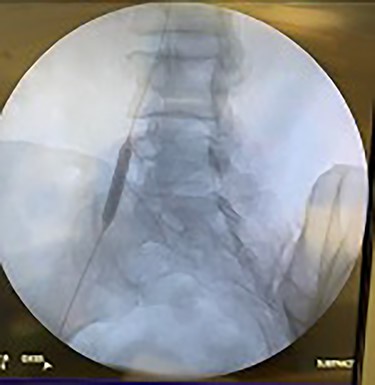

Catheter arteriogram results showed significant occlusion of the left iliac artery (Figs 3 and 4), the right iliac artery (Fig. 1), as well as the distal abdominal aorta (Fig. 2). There were numerous collateral vessels noted, indicating the presence of long-standing proximal stenosis (Fig. 1). The decision was made to use angioplasty to help widen the areas of stenosis. An 8 mm × 40 mm Passeo balloon was advanced from the right femoral artery into the left iliac artery (Fig. 7) and insufflated to 6 mmHg (Fig. 6). The balloon was allowed to remain expanded for 1 min and then was deflated. Next, the distal aorta was repaired in a similar fashion. The balloon was advanced into the distal aorta from the right femoral access and insufflated to 12 mmHg (Fig. 8). The balloon was allowed to remain expanded for 90 s.

Fluoroscopy of right iliac artery showing vast collateral vascular formation, indicating long-standing proximal obstruction.